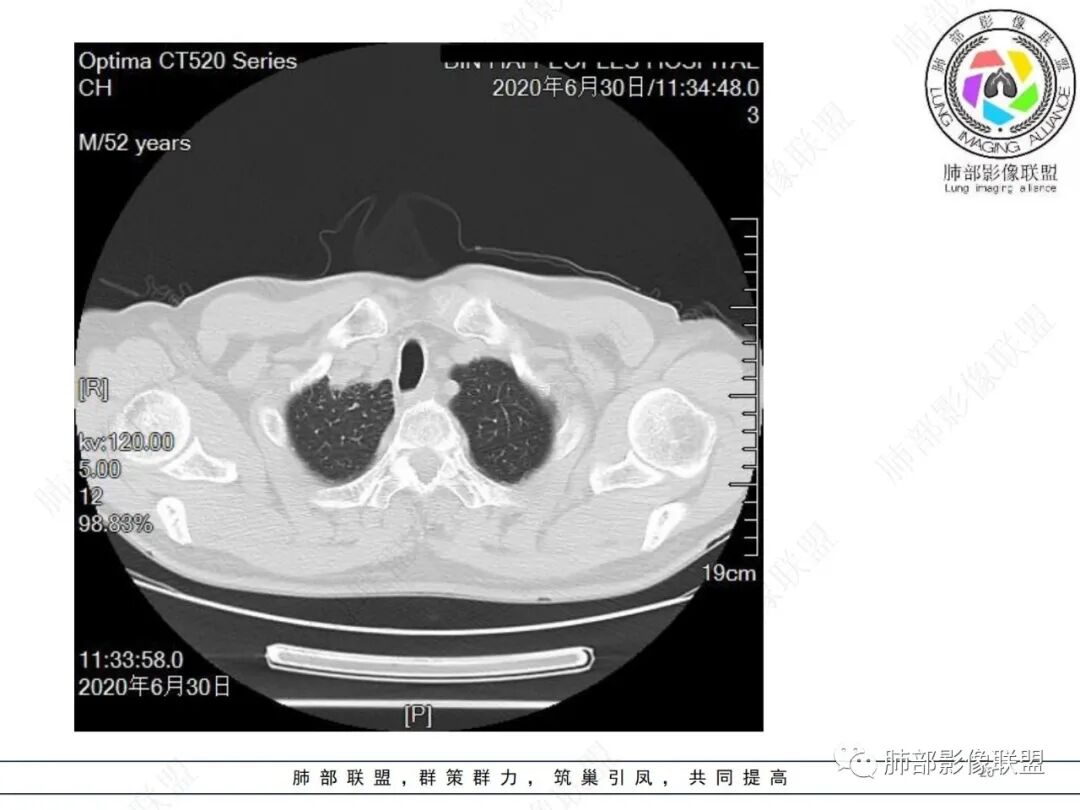

中年男性,有长期吸烟史,右肺上叶不规则肿块,边缘膨隆有分叶,支气管截断,不均匀强化,内有多灶性坏死,癌胚抗原升高,考虑肺癌可能性大,鳞癌可能。鉴别腺癌。

右肺上叶不规则形软组织密度肿块影,边缘见分叶,毛刺,病灶呈宽基底与胸膜相连,病灶内见坏死,增强扫描呈不均匀性强化,右肺上叶支气管截断,纵隔内见肿大淋巴结,肿瘤标志物增高,考虑鳞癌可能,鉴别小细胞癌,腺癌。

中年男性,长期吸烟,CT示右肺上叶肿块影,有分叶,毛刺,胸膜牵拉,支气管截断,边缘斑片影,病变内有坏死,强化,淋巴结肿大,首先考虑鳞癌可能性大,鉴别腺鳞癌

中年男性,长期吸烟,右肺上叶不规则肿块,边缘膨隆有分叶,支气管截断,不均匀强化,内有多灶性坏死,癌胚抗原升高,考虑肺癌